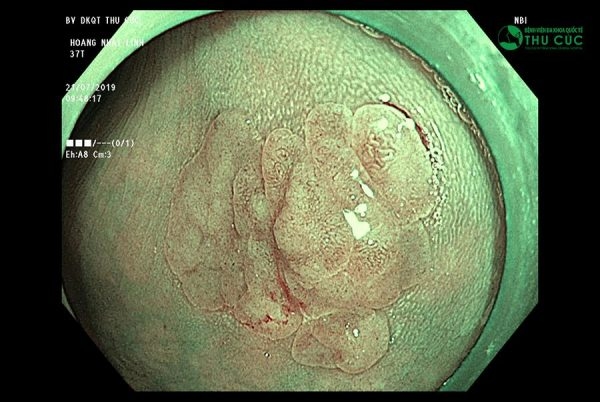

Khác với phương pháp nội soi thông thường, NBI sử dụng ánh sáng dải tần hẹp với hai bước sóng 415nm và 540nm. Điều này cho phép nội soi NBI quan sát sâu và sắc nét dưới lớp niêm mạc từ đó phân tích hình ảnh tập trung cao ở những vùng thiết yếu, phát hiện các biến đổi ở lớp bề mặt niêm mạc ống tiêu hóa và hệ thống mao mạch nông nuôi dưỡng lớp niêm mạc, phát hiện sự tăng sinh bất thường của hệ vi mạch máu nông ở vị trí khối u. Nhờ đó bác sĩ có thể phát hiện các tổn thương, khối u, tổ chức tiền ung thư ngay từ khi mới khởi phát. Đây là 1 trong những bước tiến vượt bật của NBI thế hệ mới so với nội soi thông thường.

Không chỉ có khả năng quan sát sắc nét lớp niêm mạc nhờ sử dụng ánh sáng dải tần hẹp, công nghệ nội soi NBI còn có khả năng phóng đại hình ảnh tới hơn 100 lần nhờ ứng dụng công nghệ Dual Focus hiện đại nhất thế giới, cho phép ống soi tiếp cận vị trí tổn thương ở khoảng cách gần nhất (từ 2 đến 6mm). Với ưu điểm này, nội soi NBI giúp bác sĩ dễ dàng đánh giá tổn thương bề mặt và mạch máu bên dưới đường tiêu hóa, xác định tổn thương đó có nghi ngờ ung thư hay không qua hình ảnh.

Nhờ khả năng quan sát sâu và sắc nét lớp niêm mạc và phóng đại hình ảnh tới hơn 100 lần nên công nghệ nội soi NBI sẽ dễ dàng phát hiện mọi tổn thương bệnh lý tiêu hóa bao gồm cả ung thư.

Bác sĩ CKII Phạm Thái Sơn – Trưởng đơn vị Thăm dò chức năng nội soi Bệnh viện ĐKQT Thu Cúc cho biết: “Nếu như công nghệ nội soi thường chỉ có thể phát hiện những tổn thương đã rõ nét và ở trên bề mặt thì công nghệ NBI 5P có thể nhận diện những bất thường dù là nhỏ nhất, chỉ điểm các tổ chức tiền ung thư từ rất sớm nhờ ánh sáng dải tần hẹp và khả năng phóng địa hình ảnh vượt bậc. Đây chính là giải pháp vàng giúp kiểm tra toàn diện sức khỏe tiêu hóa, sàng lọc ung thư từ giai đoạn khởi phát tăng cơ hội chữa trị cho người bệnh.”

NBI 5P có khả năng chỉ điểm khối u, phát hiện ung thư qua hình ảnh